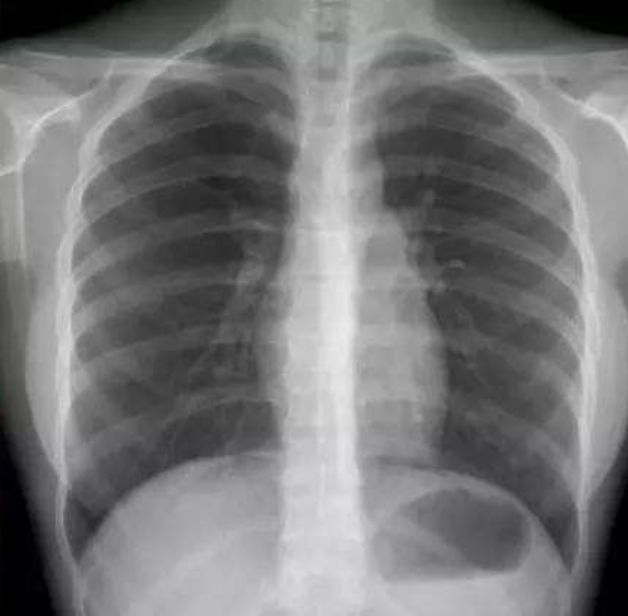

肺结节AI辅助诊断

肺癌,在我国的发病率、死亡率极高,伤害着无数家庭。在我国每年都有近60万人死于肺癌。肺癌防治的重要手段是早期筛查,其中胸部低剂量CT是国际公认的有效手段。而在如今传统的阅片模式中,医学影像面临医疗从业人员短缺,人工分析模式精准度受限,以及基层医院医疗机构诊断水平参差不齐,高年资医生匮乏,易出现漏诊、误诊等问题。

现阶段市场中的人工智能肺CT产品已经实现了肺结节的检出功能,可支持包括:实性结节、磨玻璃结节、形态不规则的大结节、血管旁结节、肺门区结节等。支持提供量化信息检测如自动测量病灶的长径、短径、CT值、体积等参数。支持提供定性信息检测如病灶密度:实性、部分实性、磨玻璃、钙化,以及病灶良恶性等级分类:良性、疑似良性、恶性、疑似恶性。另外支持多种伴随征象的检出,如边界模糊、分叶、毛刺、胸膜牵拉、血管集束等。此外还有肿块、斑片、网影、条索影、气胸、胸腔积液等病变检出。部分产品还含有胸部骨质病变筛查功能,自动检出骨折,支持3D的可视化帮助医生定位,进行全面智能分析与诊断。